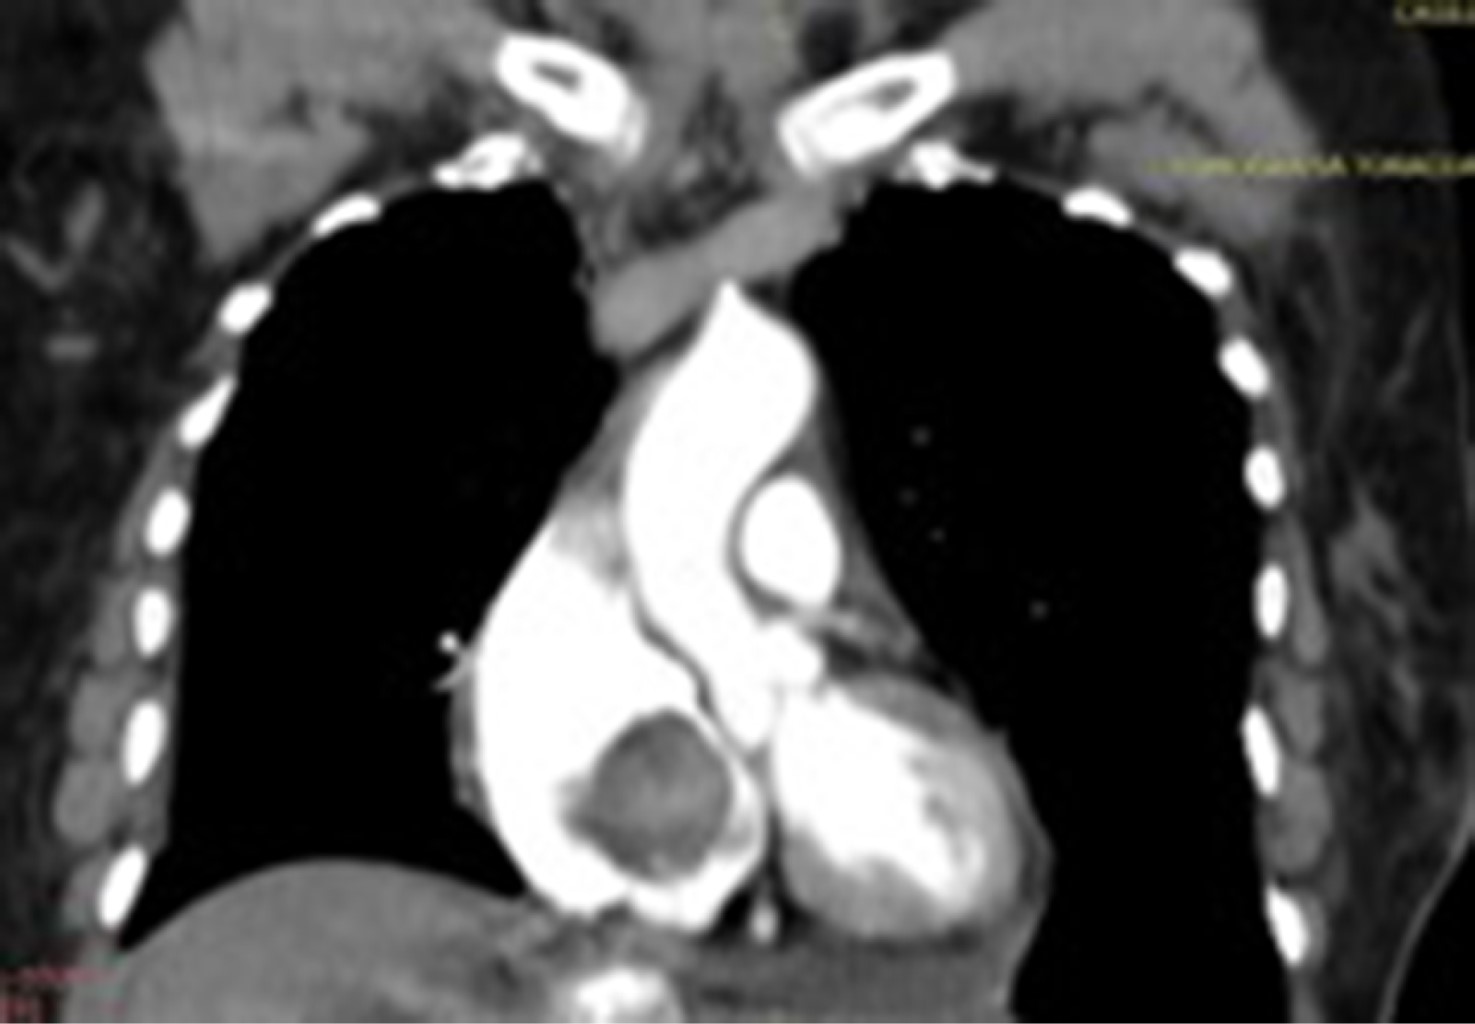

Introducción: los mixomas cardiacos son las neoplasias primarias más frecuentes del corazón. La ubicación más común es la aurícula izquierda (75%), seguido de la aurícula derecha (15-18%) y ventrículo izquierdo. Pueden presentarse con la tríada de síntomas obstructivos, embólicos y constitucionales. Caso 1: varón de 59 años en seguimiento por linfoma cutáneo no Hodgkin de linfocitos T, que padecía disnea progresiva y presentaba una masa localizada en la aurícula derecha. Se realizó resección del tumor y reemplazo de la válvula mitral debido a insuficiencia mitral severa. La histopatología confirmó el diagnóstico de mixoma. Caso 2: mujer de 61 años que consulta por trombosis en vena basílica, cefálica y yugular derecha. Un ecocardiograma mostró una masa cardiaca de 80 × 40 mm en la aurícula derecha. En el informe histopatológico se informó un mixoma cardiaco con el diámetro mayor de 7.5 cm. Fue dada de alta nueve días después de la cirugía. Conclusión: podría haber una presentación inusual de mixoma auricular que ocurra simultáneamente con una neoplasia de diferente linaje. Debe sospecharse mixoma auricular, incluso en ubicaciones inusuales e independientemente de la enfermedad neoplásica concomitante. Los fenómenos embólicos, como la primera presentación, pueden inducir a error; aunque algunos parámetros y puntuaciones pueden ser predictores útiles.

Figura 1